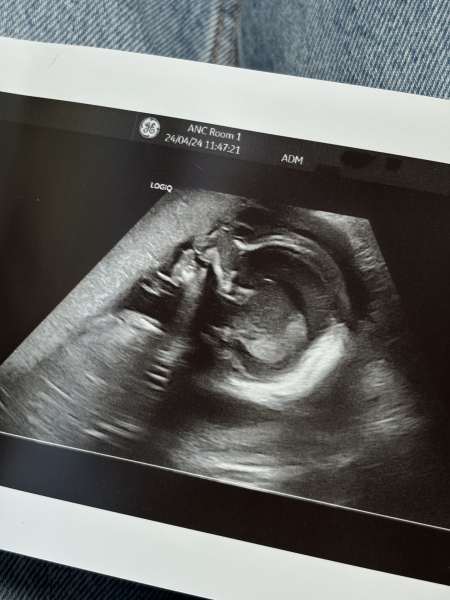

HRP1990 · 24/04/2024 12:25

Baby is perfect and measuring on the bigger side! The sonographer confirmed I do have an anterior placenta but if I am concerned about movement to make sure I speak to someone as I should still be able to feel patterns etc.

We asked for the gender to be written down, so we’ll find out soon enough! Super happy!

HRP1990 · 24/04/2024 12:27

Forgot the photo!